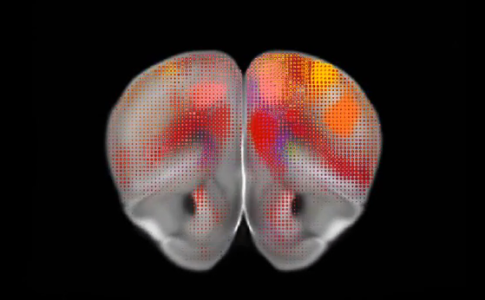

Com um detalhe nunca antes visto, o novo mapa cerebral criado por investigadores do Allen Institute for Brain Science, em ...Crânio de plástico implantado em mulher com sucesso